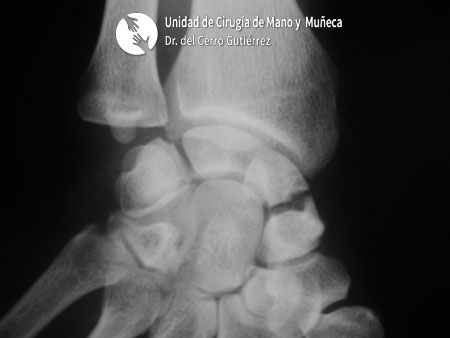

Fractura del polo proxima del escafoides de la mano

Fractura del escafoides. Polo Proximal

Fractura de escafoides de la mano. Polo Proximal